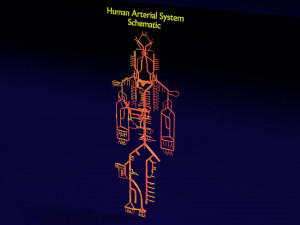

The model meshes include adult circulation versus circulation in Tetralogy of Fallot (TAF), arrow labels and text labels. The blood flow in a patient with Tetralogy of Fallot is outlined in this model. To contrast it to normal blood circulation a separate model of normal circulation is included. The Tetralogy of Fallot (OVER RIDING OF AORTA, PUL STENOSIS, VENTRICULAR SEPTAL DEFECT, RIGHT VENTRICULAR HYPERTROPHY), fossa, ligament teres , venosus, and arteriosus are duly depicted with proper labelling and blood flow directional arrows. Excellent model for teaching, demonstration and knowlegde of human body. The models include both procedural and image textures blend files separately. The texture file include diffuse, roughness and normal png and jpeg based on non overlapping UV maps.